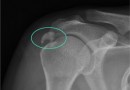

석회화 건염

어깨 힘줄에 석회가 생기는 질환으로 일단 석회가 생기면 통증이 대단히 심한 것이 특징입니다. 통증이 심해서 밤에 잠을 이룰 수 없는 정도로 돌의 크기는 갖가지 모양으로 다양합니다. 여러 개가 한꺼번에 생기는 경우도 있으며 발생원인은 힘줄에 퇴행성 손상이 생기고 …